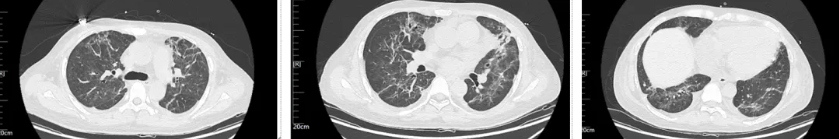

经过治疗后患者病情逐渐好转,呼吸机需氧浓度及PEEP逐渐下调,复查血气氧和指数逐渐好转,9月17日复查胸部CT(见图4),氧合指数165,予拔除气管插管,改日间高流量(流速 40L/min,氧浓度60%)与夜间无创呼吸机辅助通气(IPAP12cmH2O EPAP 5cmH2O FiO2 45%)交替,复查血气氧和指数P/F 182。予逐渐下调氧浓度复查氧和指数进一步升高(见图5),监测患者外周血感染指标超敏C反应蛋白降至基本正常(见图6)。调整鼻导管吸氧,10月7日复查胸部CT双肺慢性及间质改变较前明显吸收(见图7)。监测患者外周血KL-6水平较前明显下降(见图8)。

图7:患者2025年10月7日复查胸部CT